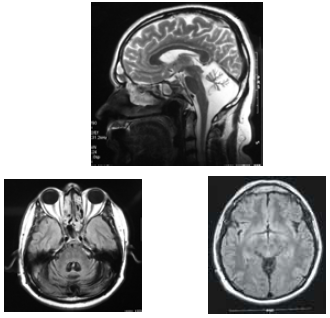

José, com 42 anos de idade, foi renovar sua carteira de motorista e, ainda na entrada do consultório, o médico observou uma marcha com base alargada e insegura. Durante a avaliação clínica, ao testar a coordenação, o médico verificou tremor de intenção à prova índex-nariz, dismetria e disdiacocinesia bilateral. Os pares cranianos, a força muscular e os reflexos — profundos e superficiais — eram normais. A fala de José era pausada, silabada. Ao ser questionado sobre o uso de álcool, negou-o e referiu que o problema do desequilíbrio vem piorando nos últimos dez anos, fato que provocou o acompanhamento médico e motivou a realização de uma ressonância nuclear magnética (RNM), cujas imagens são apresentadas abaixo.

As imagens e o quadro clínico exprimem todas alterações clássicas da doença de Machado-Joseph: patologia autossômica dominante.